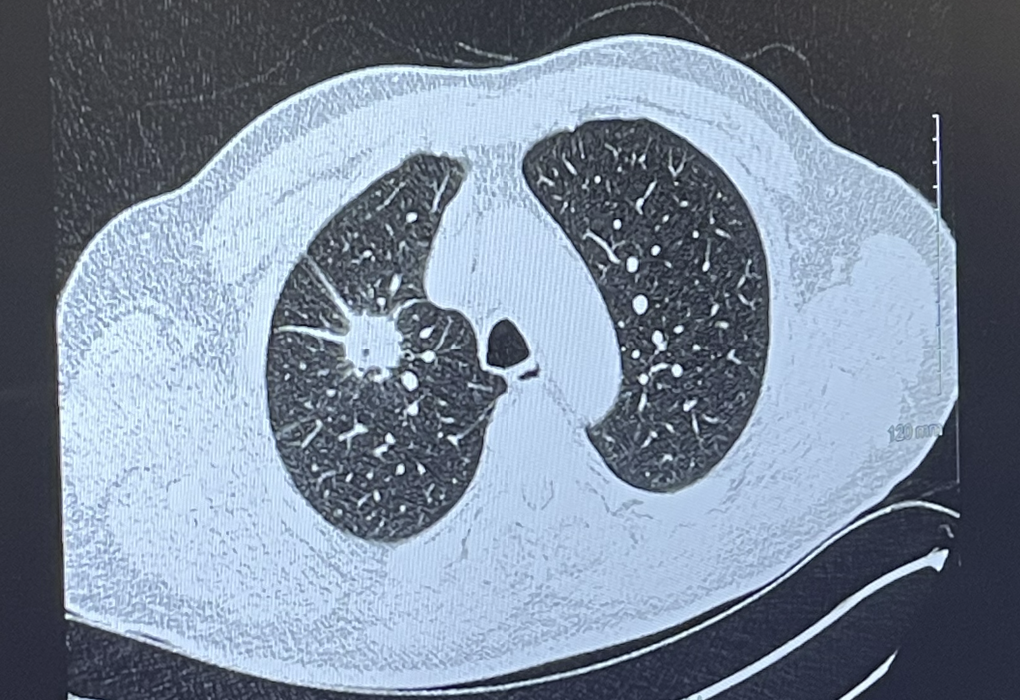

Just before Christmas 2021, I was diagnosed with lung cancer. I am and always have been a non-smoker. I had no obvious symptoms until the cancer had already metastasised into my brain, bones, lymph system and other organs. I am very lucky to have the most common form of NSCLC – non-small cell lung cancer, for which a targeted therapy (Osimertinib) was developed a decade ago. I take a tablet each day and this is working very well. My tumors are all shrinking fast and I am fortunate to have very few side effects. But it is almost inevitable that my cancer will mutate so that the therapy no longer works, and it did mutate after 18 months (June 2023) and I needed radiotherapy on an existing tumour (with a mutation that is not controlled by Osimetinib). This was successful and I continue to live life to the full.

Below is my lung tumour, when first discovered.